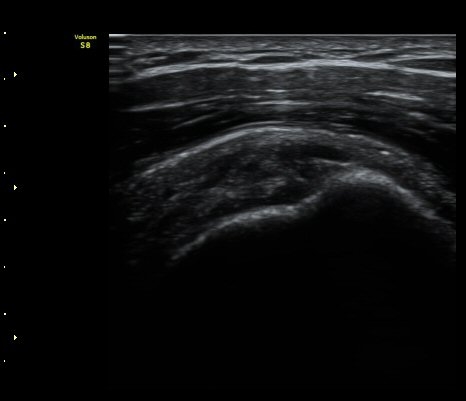

±Ø»ó°Ç Á¾´Ü¸é°Ë»ç¿¡¼­ ´ë°áÀý °Ç ºÎÂøºÎ¿¡ Àú¿¡ÄÚ °Ç °á¼ÕÀÌ °üÂûµÊ

(focal hypoechoic defect of ssupraspinatus tendon at greater tuberosity with

longitudinal scan of subscapularis tendon) »çÁø 4, 5, 6